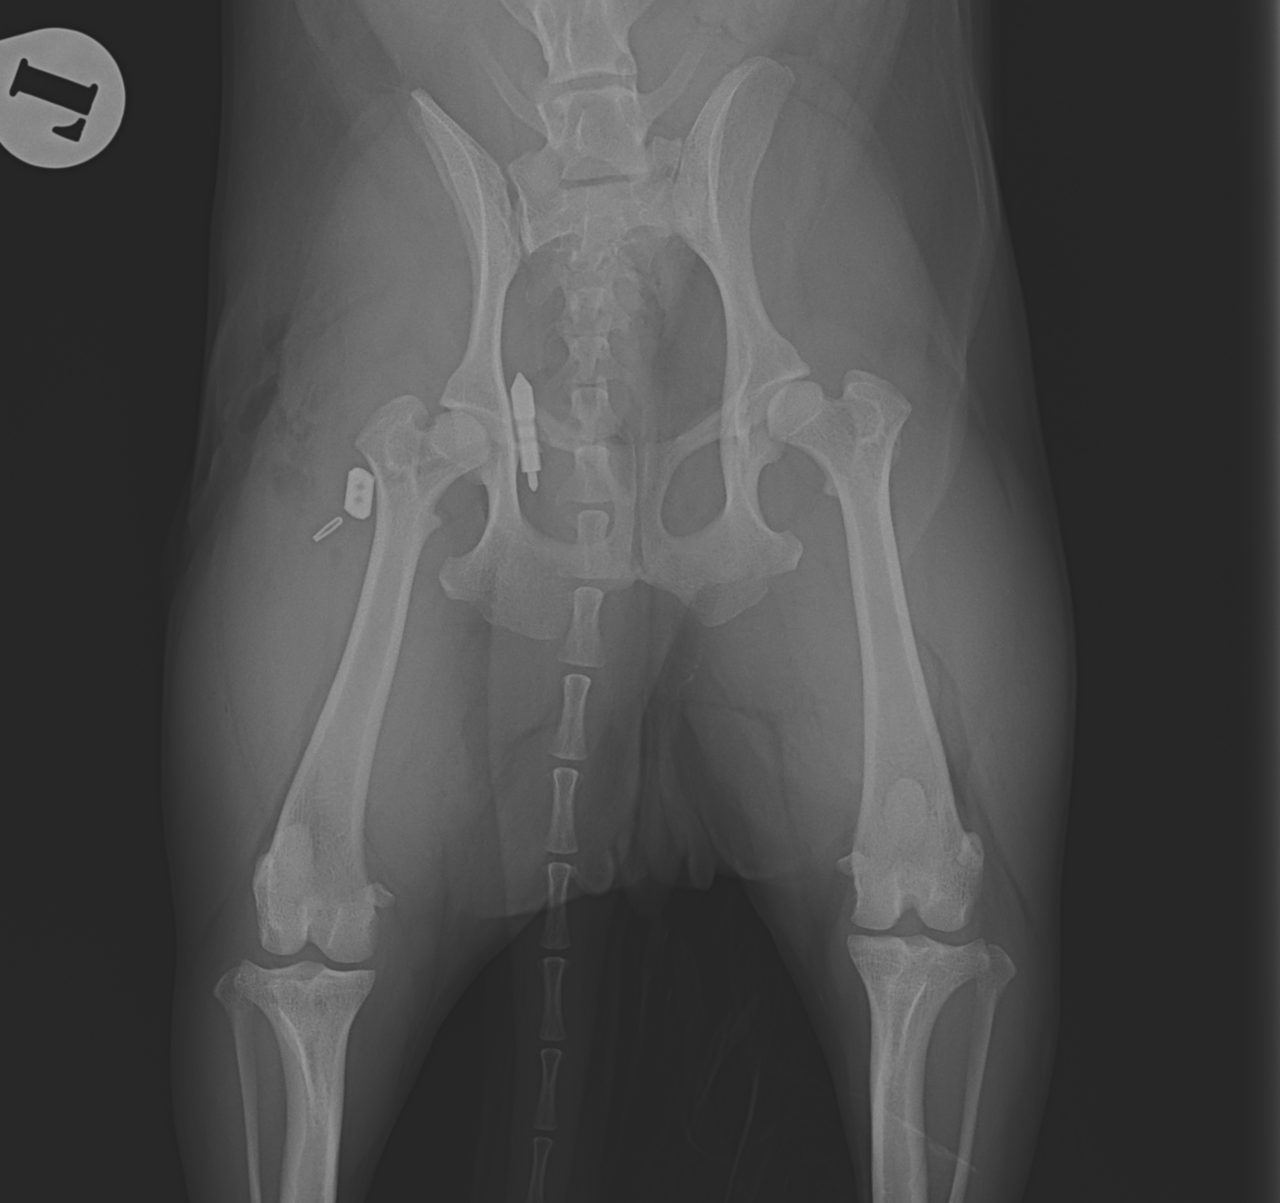

輪禍外傷による股関節脱臼の患者さんに対してBullet–Shaped Toggle Rod (BUSTOR)で整復を行いました。本症例は恥骨の骨折も併発していたため、CTで寛骨臼の評価も実施しました。低侵襲かつ短時間で整復が可能です。しばらくは安静が必要です。